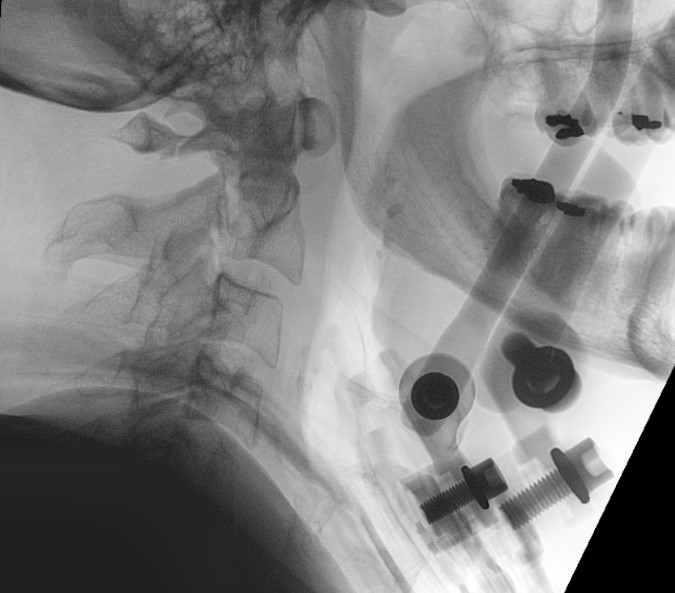

Hangman's fracture reduced and held in halo-vest

Post halo flexion and extension views demonstrating fracture stability